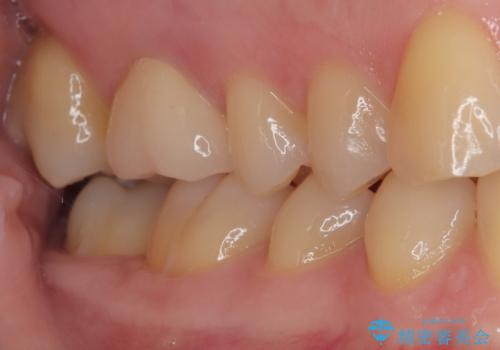

精査の結果、歯の神経は問題ないですが、欠損している範囲が大きいため部分的な詰め物では脱離や破折のリスクが高いため、オールセラミッククラウンによる補綴治療を行っていくこととしました。

適合の良い治療は再度虫歯になるリスクが低いです。